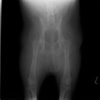

術前側面像

術前正面像

術前に25°であったTPAは、TPLO実施により7°に矯正されました。症例の歩行状態は良好です。